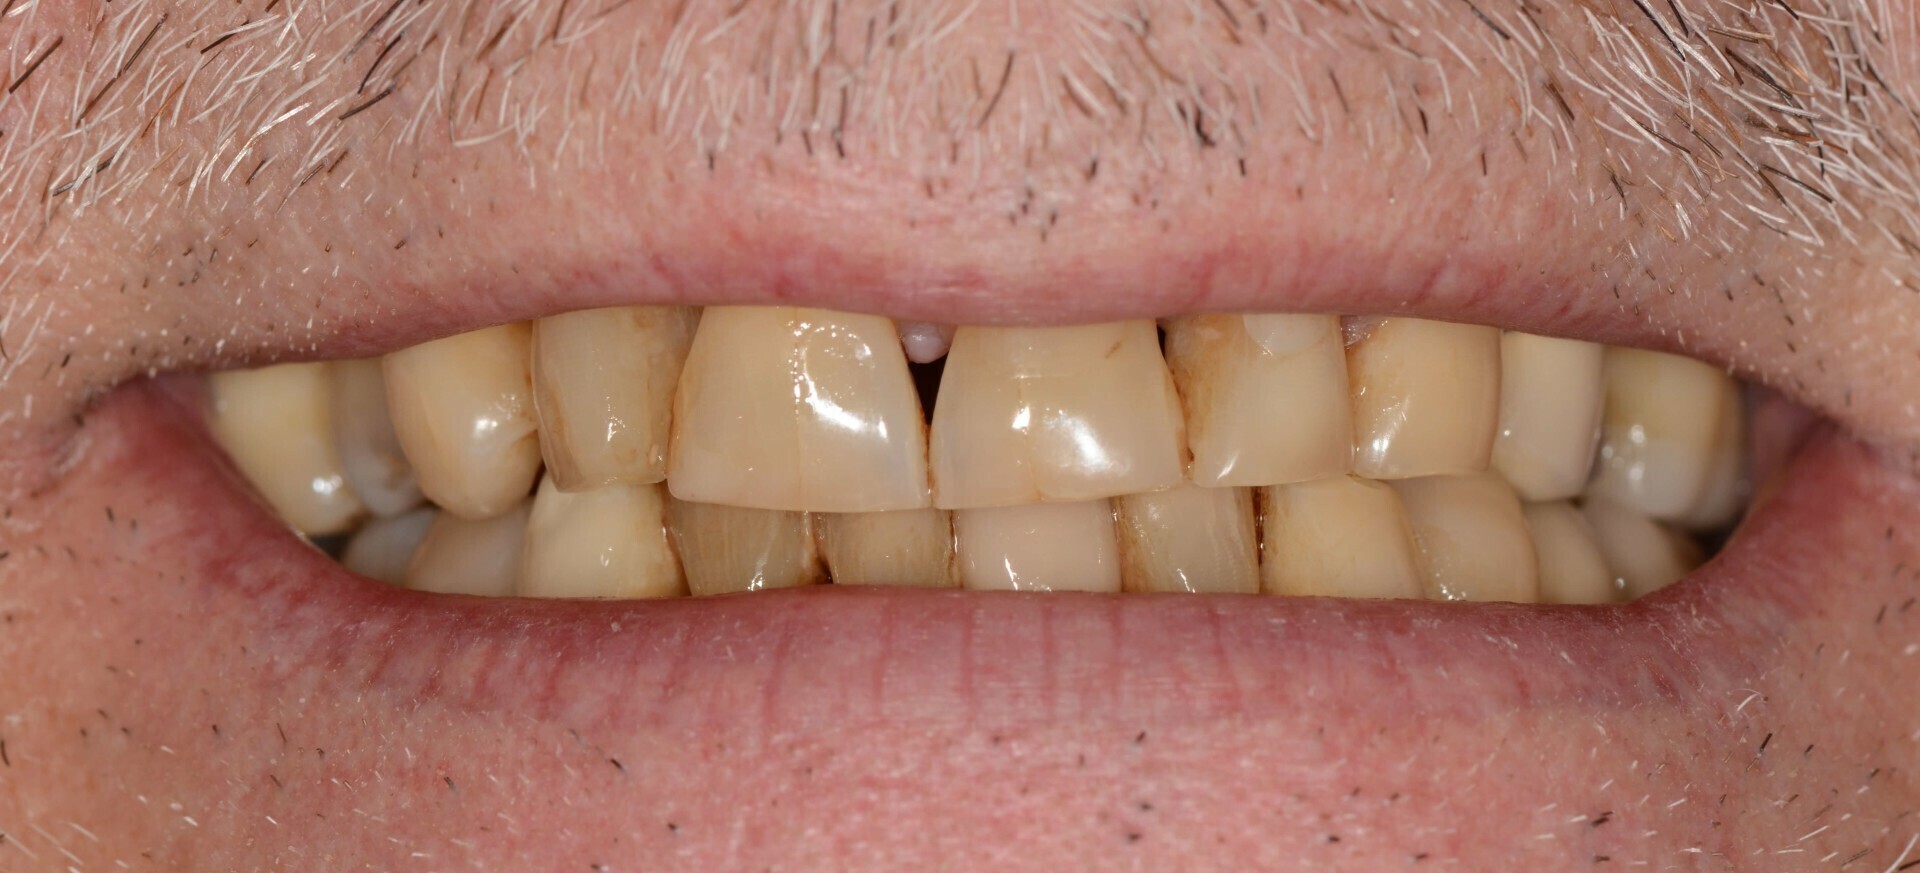

Le patient a 52 ans et il s’est usé les dents avec une brosse-à-dent très dure. Il a pensé bien faire en buvant beaucoup de jus de citron et en se faisant des bains-de-bouche à la chlorhéxidine. Nous sommes face à une abrasion d’origine mécanique et chimique et à des colorations dentaires d’origine médicamenteuse.

Des images photographiques en 2D et des images en 3D ont été couplées pour concevoir la réhabilitation du sourire et la proposer au patient.

L’occlusion (rencontre des dents) est optimisée.

Résultat final.

A l’aide d’un jeu de maquettes et d’usinage, les restaurations respectent le projet initial.